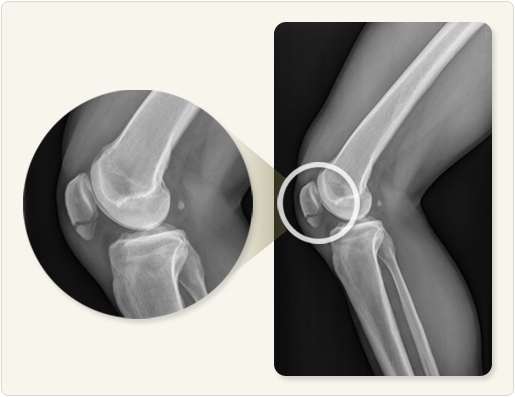

슬개골은 무릎 앞쪽에 위치한 뼈로, 강한 외상이나 낙상 등으로 골절이 발생할 수 있습니다. 수술로 고정한 이후 회복은 3개월 이상 걸릴 수 있으며, 회복 속도는 개인의 체력, 재활 순응도, 수술 방식 등에 따라 달라집니다. 최근에는 물리치료와 자가운동 프로그램을 조기부터 병행함으로써 회복을 앞당기는 사례가 늘고 있습니다. 따라서 단계별 관리가 무엇보다 중요합니다.